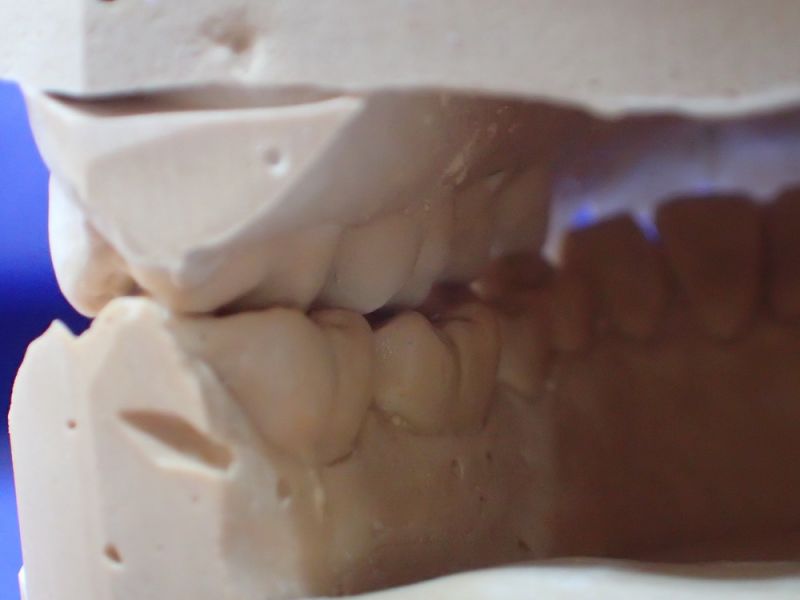

Mann kann hier sehr gut an den beiden Punkten der distalen Dreipunktabstützung erkennen, mit welch hoher Passgenauigkeit die Zentrikplatten auf die Gipszähne der Meistermodelle aufgebacht werden können und müssen.

Es ist einer dieser Detailpunkte, der darüber entscheidet, mit welcher Anfangspassgenauigkeit ein 'A'ufbissbehelf am Ende eines langwierigen Arbeitsprozesses in der Mundhöhle des Patienten eingeglidert werden kann.